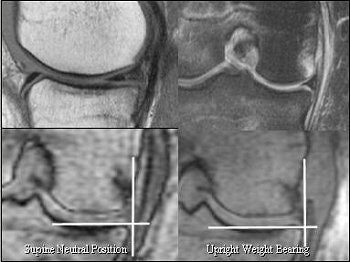

![]() |

| Partially torn MCL with medial subluxation of medial meniscus. On the basis of MR measurements, no meniscal displacement was judged to be present in the supine 90° flexed position with external rotation or in the upright weight-bearing position. |